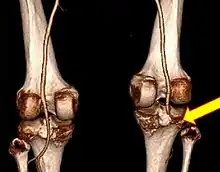

![]() | |

| Plain lateral X-ray of the left knee showing a posterior knee dislocation[1] | |